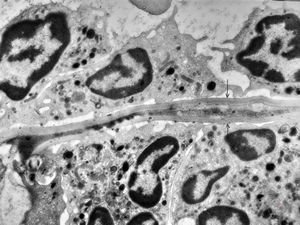

M,62y. | bone marrow - plasmocytoma

M,64y. | bone marrow - plasmocytoma

bone marrow … plasmocytoma (parafin-embedded sample)